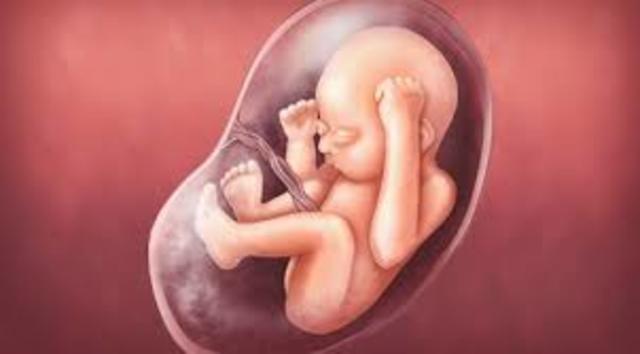

• continued to the  period of fetus

continued to the period of fetus

Second trimester and could be a viable birth. starts-at around week 15 it is the size of an apple. It can now move its joints. Week 20 its the size of a banana. Baby's legs are curled up against its torso. Also you can know what sex its going to be.

• fetus

fetus

Week 21, its 10 1/2 inches long. size of a carrot.